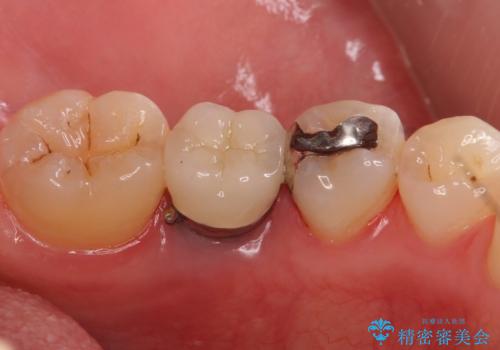

銀の詰め物 セラミックへのやり替え

- 下の奥の銀歯を白くしたいとのことで来院されました。

セラミックインレーでの治療を行いました。

- 左下5 セラミックインレー 77,000円費用は治療当時の料金となります

銀の詰め物のやり替えは2回の来院で終わらせることができます。